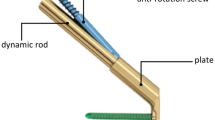

Combined with CS’s less invasiveness and the DHS’s stability, Depuy Synthes medical device company has developed a brand new product, the Femoral Neck System (FNS). Its design strategy is to reduce the incidence of complications and secondary surgery by increasing stability, reducing invasiveness, and reducing the risk of lateral protrusion. Currently, the operation of femoral neck fractures treated with FNS has been performed clinically, and specific therapeutic effects have been observed.

FNS: Referring to the Femoral Neck System Surgical Technique provided by Depuy Synthes, the FNS model was constructed in SolidWorks 2017 software.

CS: Referring to the implants in the 6.5 mm and 7.3 mm cannulated screw system provided by Depuy Synthes Medical Company, the CS model was constructed (Table 1).

Subsequent research will set the screw and the bone in a binding contract relationship. The thread has little effect on the experimental results, so the threaded part is removed. The thread is provided with a smooth surface, the diameter of which corresponds to the thread diameter (Fig. 1b).